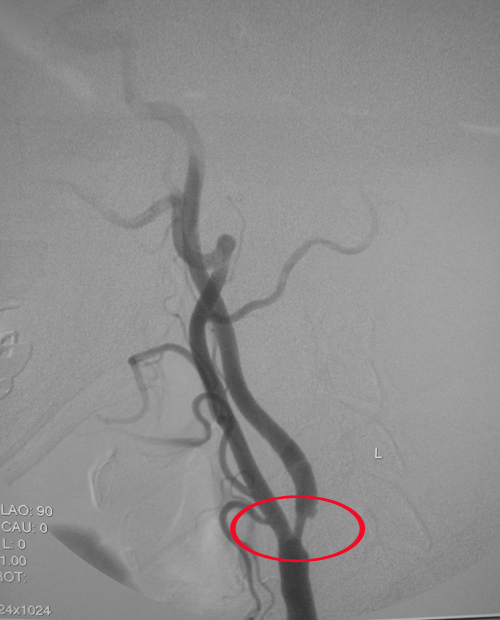

患者三:张某,男性,51岁,主因右眼视物不清1年余,左眼视物不清2月,发现双侧颈动脉狭窄1月入院。患者1年多前发现右眼视物不清,就诊于外院,诊为“眼底出血”,经治疗好转,视力恢复至0.6-0.7。2月前患者突发左眼视物不清,再次入院就诊,诊断为“糖尿病视网膜病变”。1月前,查颈动脉超声示“双侧颈动脉狭窄”,为行脑血管造影以“颈动脉狭窄”收入院。既往高血压史1年,血压最高达170/120mmHg;糖尿病史1年余;脂肪肝史,颈椎外伤史13年。吸烟20余年,约20支每日,6年前戒除;饮酒20余年,约白酒4两每日,1年前戒除。全脑血管及弓上动脉造影示:左侧颈内动脉C1段重度狭窄,右侧颈外动脉起始段重度狭窄70%。

入院诊断:1、双侧颈动脉狭窄 ;2、2型糖尿病 糖尿病视网膜病变;3、高血压病3级,极高危组;4、脂肪肝;5、右眼结膜下出血。

处理方法:左侧颈内动脉作为病变较重的一侧,同时,因颈内动脉没有分支,一旦闭塞,后果将很严重,也支持先处理左侧颈内动脉病变。2009年1月15日上午张某顺利接受了左侧颈内动脉内膜剥脱术。术后症状完全消失,右眼视力由术前的0.2恢复至0.4。